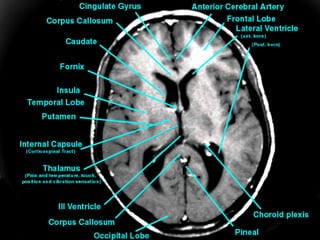

Thalamus  The thalamus consists of two masses of nerve cells and fibres situated withing he cerebral hemispheres just below the corpus callosum one on each side of the third ventricle  This region contains a cluster of nuclei Most of the sensory inputs are conducted to the cerebral cortex through the thalamus  Axons carrying auditory, visual and other sensory informations synapse with specific nuclei of this region This region may also influence mood and general body movements due to strong emotions such as fear or anger

Basal Ganglia This area of grey matter lies deep within the cerebral hemispheres Consist of  the  caudate nucleus ,  putamen  and  globus pallidus .  They are functionally important for  controlling voluntary movements and establishing postures .  It influences skeletal muscle tone When they are altered - say in disorders like Huntington disease or Wilson disease - the person has unwanted movements, such as involuntary jerking movements of an arm or leg or spasmodic movement of facial muscles.

The  caudate   nucleus  and  putamen  along with the interposed anterior limb of the internal capsule are collectively known as the  corpus striatum  (i.e. striated body) because of their appearance.  Similarly, the shape of the  putamen  and  globus   pallidus  resembles a lens, and they are collectively called the  lenticular nucleus .

Internal Capsule Consists of  projection   fibres  – fibres connecting the cerebral cortex with the lower parts of the brain and the spinal cord Lies deep within the brain Between   the basal ganglia and the thalamus All the  impulses  passing  to and from the cerebral   cortex  are carried by the fibres in the internal capsule The motor fibres within the internal capsule form the  pyramidal   tracts  (otherwise called the corticospinal tracts) The pyramidal fibres cross to the other side at the level of the medulla oblongata (called  decussation )

Thalamus Thethalamus consists of two masses of nerve cells and fibres situated withing he cerebral hemispheres just below the corpus callosum one on each side of the third ventricle This region contains a cluster of nuclei Most of the sensory inputs are conducted to the cerebral cortex through the thalamus Axons carrying auditory, visual and other sensory informations synapse with specific nuclei of this region This region may also influence mood and general body movements due to strong emotions such as fear or anger

Basal Ganglia Thisarea of grey matter lies deep within the cerebral hemispheres Consist of the caudate nucleus , putamen and globus pallidus . They are functionally important for controlling voluntary movements and establishing postures . It influences skeletal muscle tone When they are altered - say in disorders like Huntington disease or Wilson disease - the person has unwanted movements, such as involuntary jerking movements of an arm or leg or spasmodic movement of facial muscles.

Internal Capsule Consistsof projection fibres – fibres connecting the cerebral cortex with the lower parts of the brain and the spinal cord Lies deep within the brain Between the basal ganglia and the thalamus All the impulses passing to and from the cerebral cortex are carried by the fibres in the internal capsule The motor fibres within the internal capsule form the pyramidal tracts (otherwise called the corticospinal tracts) The pyramidal fibres cross to the other side at the level of the medulla oblongata (called decussation )